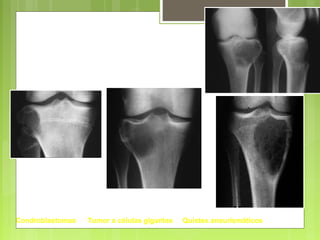

Condroblastomas Tumor a células gigantes Quistes aneurismáticos

Epífisis

Condroblastomas Tumor acélulas gigantes Quistes aneurismáticos Epífisis